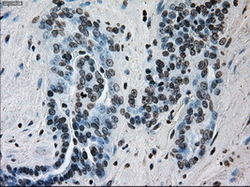

- Immunohistochemical staining of paraffin-embedded bladder tissue using anti-ERCC1 mouse monoclonal antibody. (Dilution 1:50).

- Submitted by

- LSBio (provider)

- Enhanced method

- Genetic validation

- Main image

- Experimental details

- Immunohistochemical staining of paraffin-embedded Carcinoma of bladder tissue using anti-ERCC1 mouse monoclonal antibody. (Dilution 1:50).